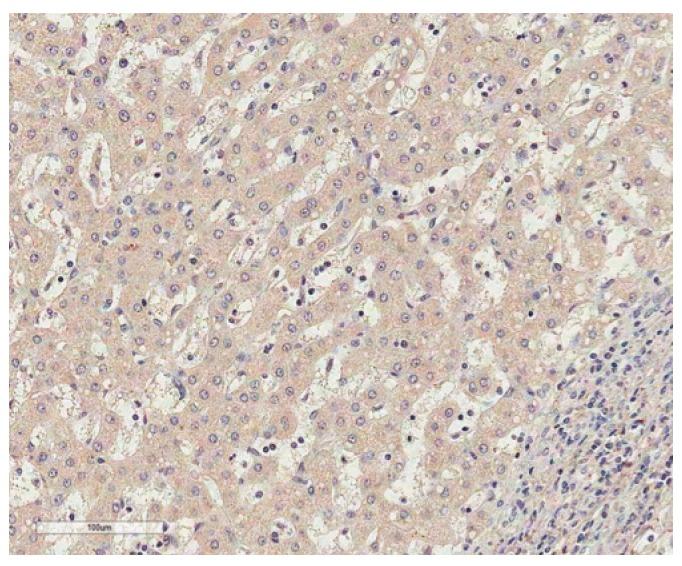

PEG10 protein expression was examined by immunohistochemistry in tumor tissues from 218 HCC patients undergoing curative resection. Furthermore, the relationships between PEG10 expression and clinicopathologic features or postoperative survival of HCC patients were evaluated. The median follow-up period was 119.8 months for survivors.

PEG10 expression was observed in 148 of the 218 HCCs (67.9%) and was significantly correlated with younger age, female, higher Edmondson grade, microvascular invasion, intrahepatic metastasis, higher American Joint Committee on Cancer T-stage, and higher α-fetoprotein level. PEG10 expression was an independent predictor of early recurrence (p=0.013), and it showed an unfavorable influence on recurrence-free survival (p < 0.001). A subgroup analysis showed that among patients with α-fetoprotein ≤ 20 ng/mL (80 patients), the PEG10-positive group also showed an unfavorable influence on recurrence-free survival (p=0.002). Moreover, a multivariate survival analysis identified PEG10 as an independent predictor of shorter recurrence-free survival (p=0.005). PEG10 expression showed an unfavorable influence on overall survival (p=0.007) but was not an independent predictor of shorter overall survival (p=0.128).

采用免疫组织化学法检测218例行根治性切除的HCC患者肿瘤组织中PEG10蛋白的表达。此外,评估PEG10表达与HCC患者临床病理特征或术后生存的关系。幸存者的中位随访期为119.8个月。

218例HCC中有148例(67.9%)观察到PEG10表达,且与较年轻年龄、女性、较高的Edmondson分级、微血管侵犯、肝内转移、较高的美国癌症联合委员会T分期以及较高的甲胎蛋白水平显著相关。PEG10表达是早期复发的独立预测因素(p = 0.013),对无复发生存有不利影响(p < 0.001)。亚组分析显示,在甲胎蛋白≤20 ng/mL的患者(80例)中,PEG10阳性组对无复发生存也有不利影响(p = 0.002)。此外,多因素生存分析确定PEG10是无复发生存期较短的独立预测因素(p = 0.005)。PEG10表达对总生存有不利影响(p = 0.007),但不是总生存期较短的独立预测因素(p = 0.128)。